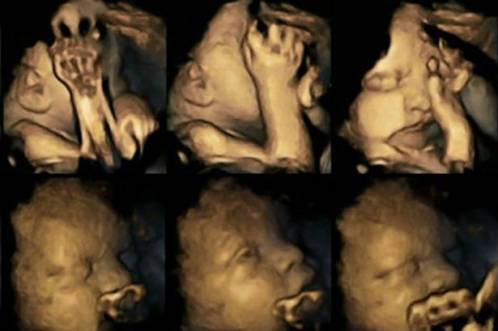

Decir que fumar en el embarazo es perjudicial no es ninguna novedad. Es un hecho demostrado y probado que los hijos de madres fumadoras tienen más complicaciones y problemas de salud. Se habla mucho de los efectos del tabaco sobre los niños, pero ahora un grupo de científicos de la Universidad de Durham han demostrado esos efectos sobre los bebés en el útero materno a través de una serie de ecografías.

A través de unas ecografías en 4D se ha podido observar una secuencia de movimientos distinta entre los bebés de mamás fumadoras y mamás no fumadoras. Los bebés de madres que consumían cigarrillos movían mucho más la boca y se tocaban la cara con más frecuencia que los bebés de mamás no fumadoras.

Los doctores que han llevado a cabo estas pruebas esperan que sirvan para concienciar a las mujeres de dejar el tabaco durante la gestación. Ninguno de los bebés que formaron parte de este estudio tuvieron problemas al nacer, sin embargo, los efectos de la nicotina pueden provocar el nacimiento sin vida del bebé.